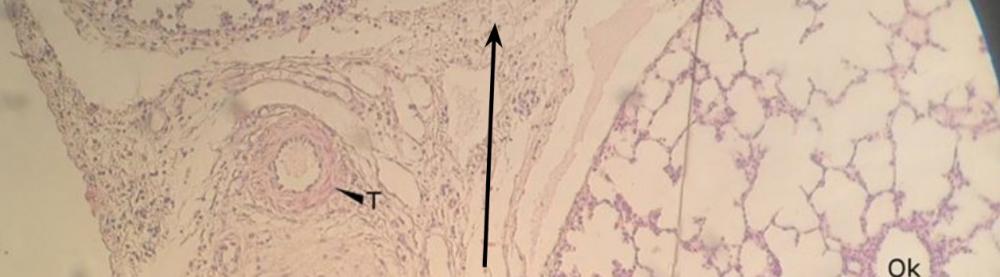

Pytanie 287

po lewej - tętnica typu sprężystego - płucna - czynnościowa, po prawej - tętnica typu mięśniowego - oskrzelowa - odżywcza (płuco, barwienie fuksyną paraaldehydową i eozyną)